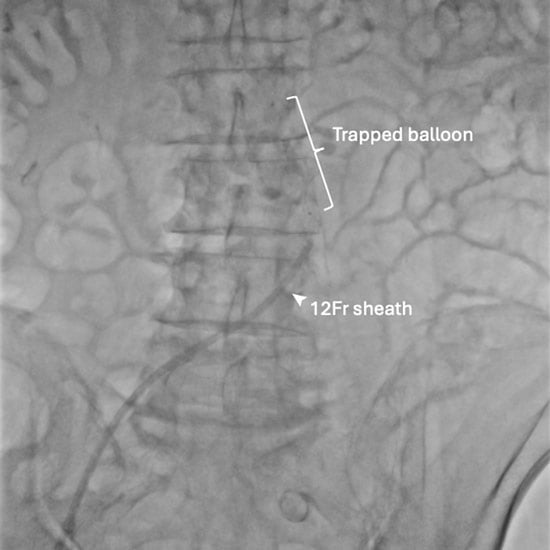

An 81-year-old male patient with symptomatic severe aortic stenosis was admitted for transcatheter aortic valve intervention via right radial and femoral accesses. The native aortic valve was predilated with a 24-mm TrueTM balloon (BD, Franklin Lakes, NJ, USA), delivered via a 12F sheath. The deflated balloon could not be retrieved. Further withdrawal resulted in concertina of the sheath (Figure 1A).

Figure 1. Bailout for aortic valvuloplasty balloon entrapment with schematic illustration of the procedure.

Figure 1A: Failed balloon retrieval.